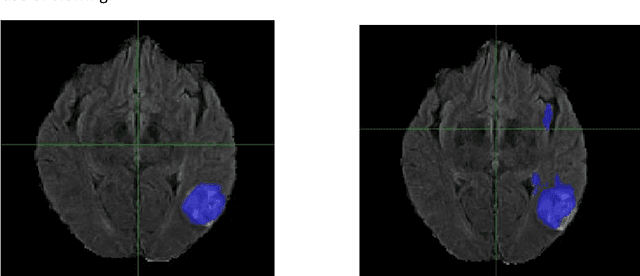

Abstract:Prostate cancer (PCa) is the most common cancer in men in the United States. Multiparametic magnetic resonance imaging (mp-MRI) has been explored by many researchers to targeted prostate biopsies and radiation therapy. However, assessment on mp-MRI can be subjective, development of computer-aided diagnosis systems to automatically delineate the prostate gland and the intraprostratic lesions (ILs) becomes important to facilitate with radiologists in clinical practice. In this paper, we first study the implementation of the Mask-RCNN model to segment the prostate and ILs. We trained and evaluated models on 120 patients from two different cohorts of patients. We also used 2D U-Net and 3D U-Net as benchmarks to segment the prostate and compared the model's performance. The contour variability of ILs using the algorithm was also benchmarked against the interobserver variability between two different radiation oncologists on 19 patients. Our results indicate that the Mask-RCNN model is able to reach state-of-art performance in the prostate segmentation and outperforms several competitive baselines in ILs segmentation.